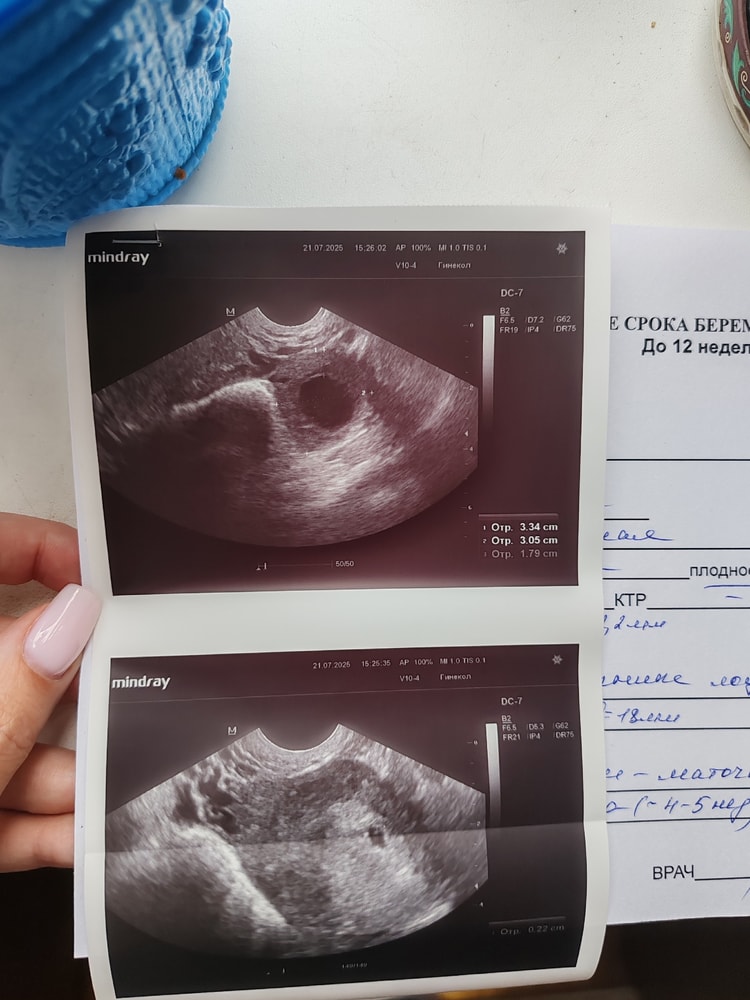

В 5,2 плодное яйцо 5мм, в 8,0 ктр 1,5см, в 12,3 ктр 6,0см.

Елизавета, да, с хгч все правильно поняли. Т.е. через 6 дней после него увидели ПЯ 7мм

УЗИ ваше соответствует сроку,в две беременности ходила на УЗИ в 5,1 акушерских ( 22 дпо) в одну пя 7 мм было даже жм ещё не было,в другую 8 мм и жм 1,6,через 9 дней в 6,3 акушерских пя 19,ктр 5,4 и ЧСС 146 уд/мин